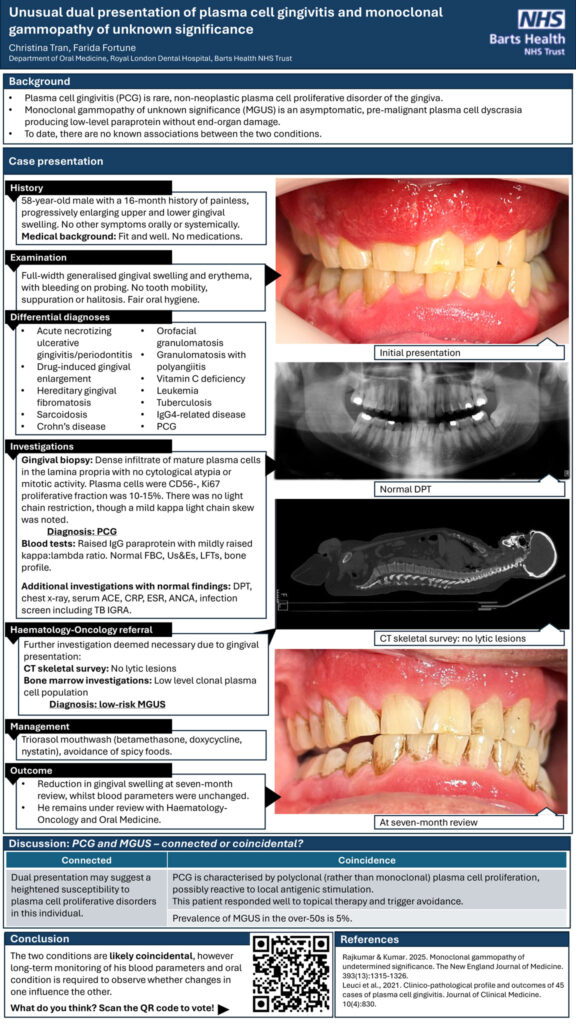

Unusual dual presentation of plasma cell gingivitis and monoclonal gammopathy of unknown significance